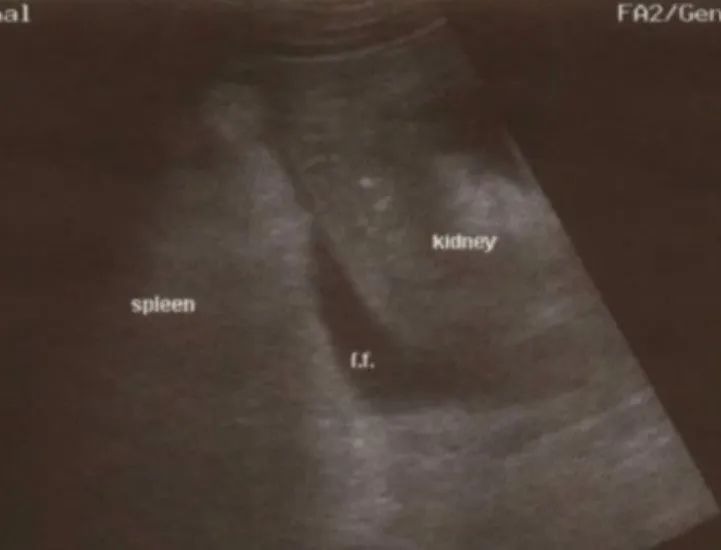

脾肾间隙和左肺底:像检查肝肾隐窝一样,将探头成角度地放置于患者的左上腹,但位置可能会更高(9~10肋)、更靠后,大约在腋后线的位置。脾可能比想象的位置更高、更靠后,比肝更难显示。对能够配合的患者,令其深呼吸,这样有利于获得清晰的图像。参照上述扫查方法,变化扫查角度,直到获得显示左肾、脾、膈肌和左肺底的清晰图像。游离积液显示为一黑色带样结构,位于脾肾间隙,或位于脾与膈肌之间(膈下游离积液)。

注:脾肾隐窝积液